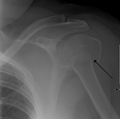

Fracture of the proximal humerus with involvement of the greater tubercle

Proximal humerus fracture